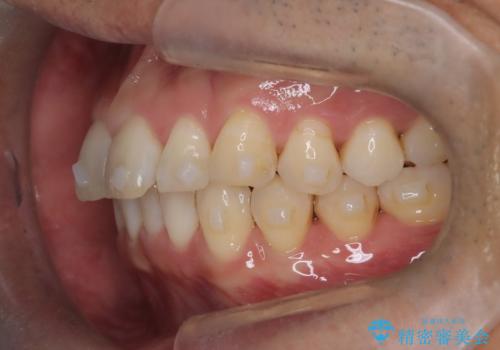

【インザライン】前歯の凸凹を治したい

- 前歯の凸凹を主訴に来院されました。

下顎位が右方に変異しており、外科矯正も提案しましたが患者様は希望されず、インビザラインにて治療を完了しております。

叢生のスペースを確保するために、臼歯部の遠心移動を行っています。

今回の治療計画は上顎の正中を顔と揃えることを優先しています。